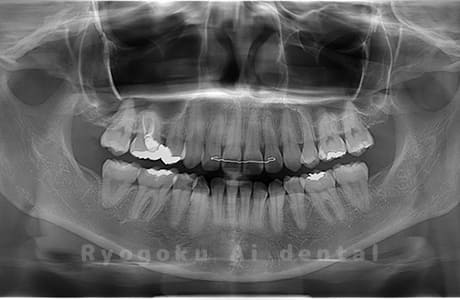

Case01

- 原因

- 水平埋伏智歯

- 治療内容

- 下顎の水平埋伏智歯を抜歯

<リスク・副作用>

手術後は痛み、腫れ、痺れなどの副作用が生じる場合があります。